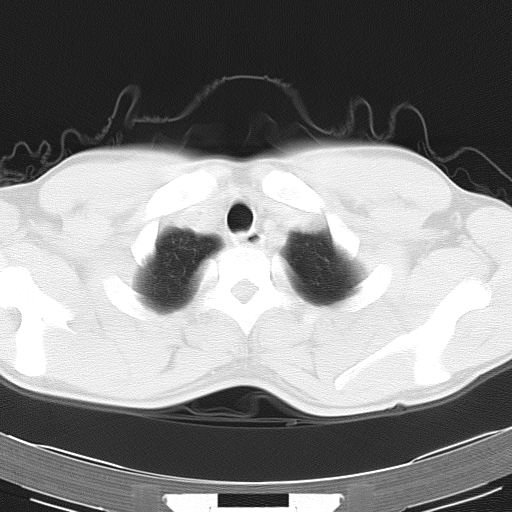

两上肺磨玻璃样改变,均位于肺外周,考虑1、肺泡蛋白沉着症?2、肺泡炎?请询问有无养鸟史 3、脱屑性间质性肺炎?建议进一步检查、复查随访

两上肺的ggo,靠近胸膜,不是以节段分布,青年男性,个人意见为吸入性的真菌感染可能为大------------呼吸内科医生

两肺上叶近胸膜磨玻璃样阴影,考虑1、炎性病变。 。2、过敏性炎症?

病灶特点:

分布在肺野的外带,病灶边缘清楚,病灶以磨玻璃影为主夹杂少许纤维状高密度影

支持zhangzhongshou主任,考虑蛋白沉着症可能性大

(1)斑片状磨玻璃影:指肺野密度朦胧增加,内可见肺血管纹理影,系肺泡腔内充满低密度的磷脂蛋白物质所致。

(2)其内部小叶间隔或小叶内间隔增厚所形成的网格状影,为小叶间隔水肿、肺泡壁内淋巴细胞和巨噬细胞浸润以及小叶内淋巴管扩张的缘故。

(3)病灶边缘清楚,呈地图样分布于肺野外围或肺门及中央区。

肺泡蛋白沉积症;胸膜下区磨玻璃样,实变区见纹理走形,地图样改变。做mri。

ct表现 (1)中央型:表现为蝶翼状浸润性阴影对称分布于两侧肺门周围,其内可见支气管充气征,病变区与正常肺组织分界清楚。(2)外围型:表现为多发性条片状、斑片状及斑块状高密度影,弥散、对称或不对称分布于两肺或一侧肺外围部位。病变区与正常肺组织及脏层胸膜面分界清晰,呈地图样改变。hrct可显示小叶间隔增厚及肺小叶内淡淡的密度增高影等细微结构,同时易发现肺大疱、肺气囊及节段性肺不张。

再仔细阅读该病人的ct片,我们不难发现,病例所表现的正是外围型的肺泡蛋白沉积症表现,即:为多发性条片状、斑片状及斑块状高密度影,弥散、对称或不对称分布于两肺或一侧肺外围部位。病变区与正常肺组织及脏层胸膜面分界清晰,呈地图样改变。